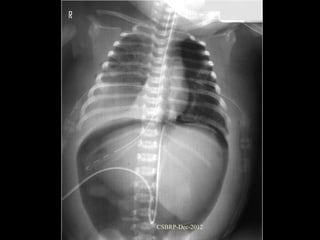

Bronchiectasis, secondary

the right middle lobe.

Bronchiectasis, secondary to obstruction involving the right middle lobe. CSBRP-Dec-2012